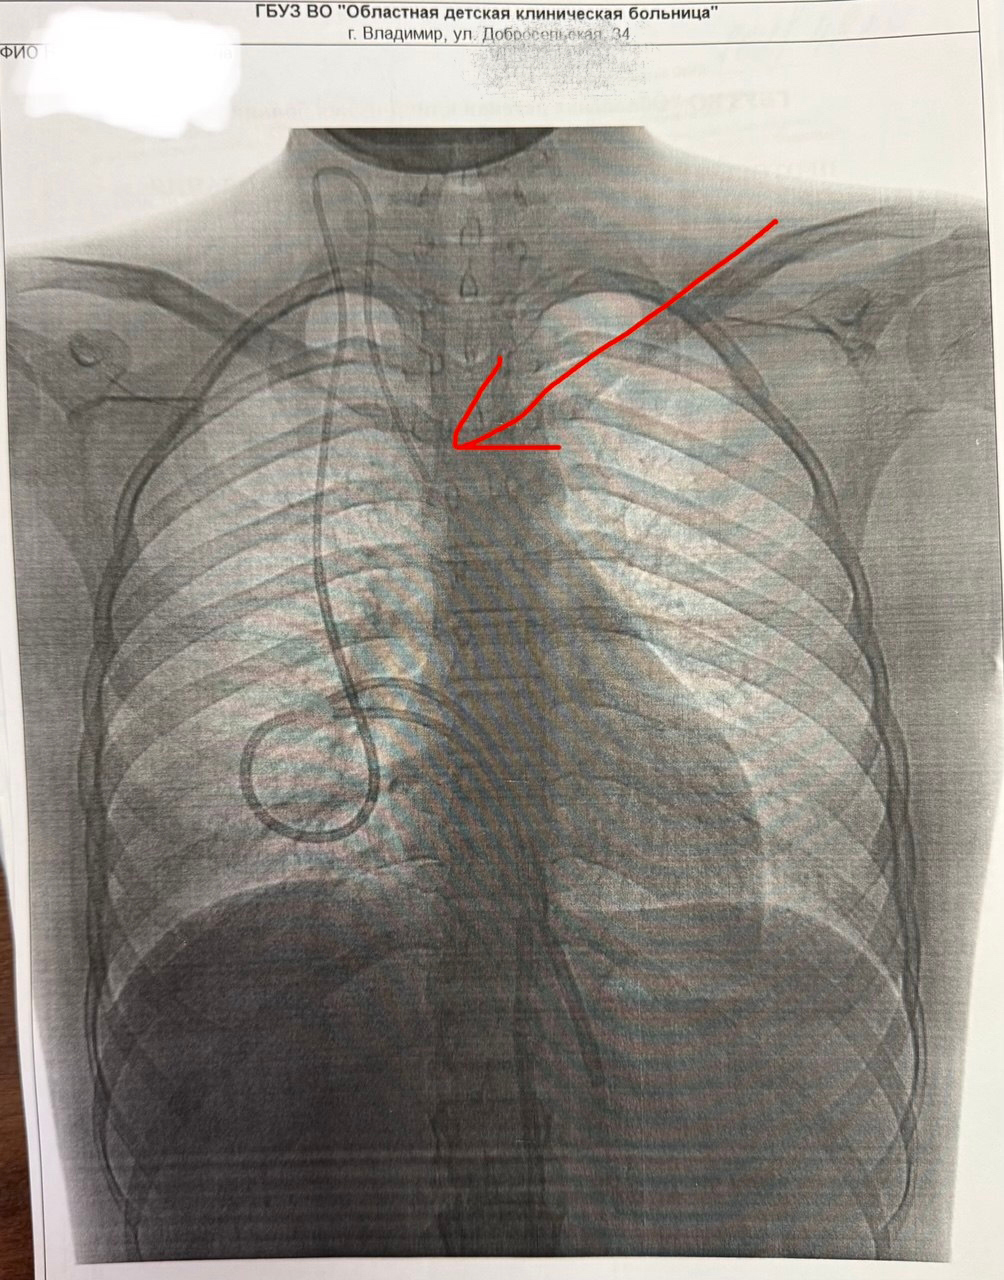

1. PICC-line катетер) имплантируется в плечевую вену на уровне нижней трети плеча и проводится до верхней полой вены. Срок его службы от трех до шести месяцев.

2. Тунелируемые катетеры, которые обычно заходят в верхнюю полую вену через яремную вену, он проводится под кожей и выводится в грудную клетку. Он может использоваться до года.

3. Импланитруемая порт-система, которая находится полностью под кожей и может применяться до пяти лет.